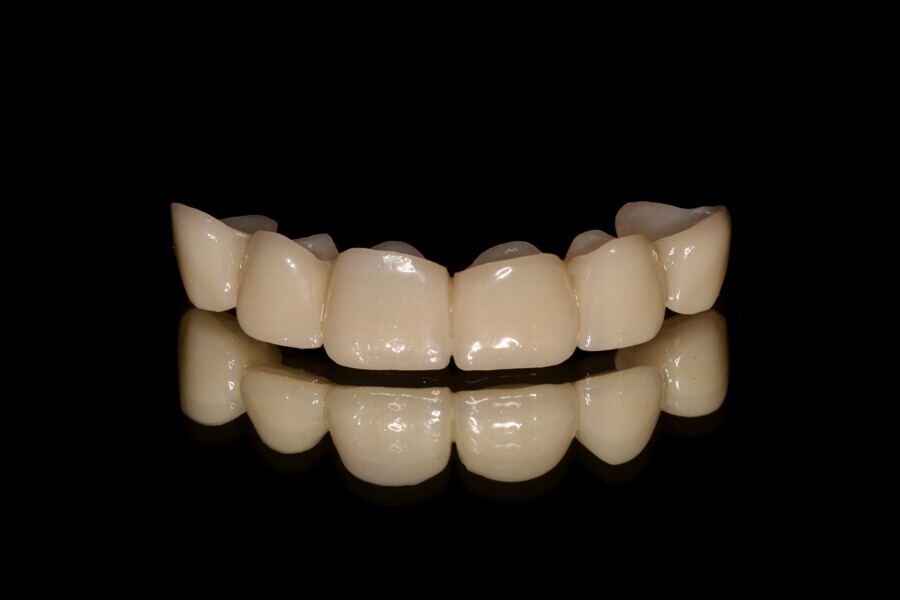

Fig. 13: Final lithium disilicate restorations.